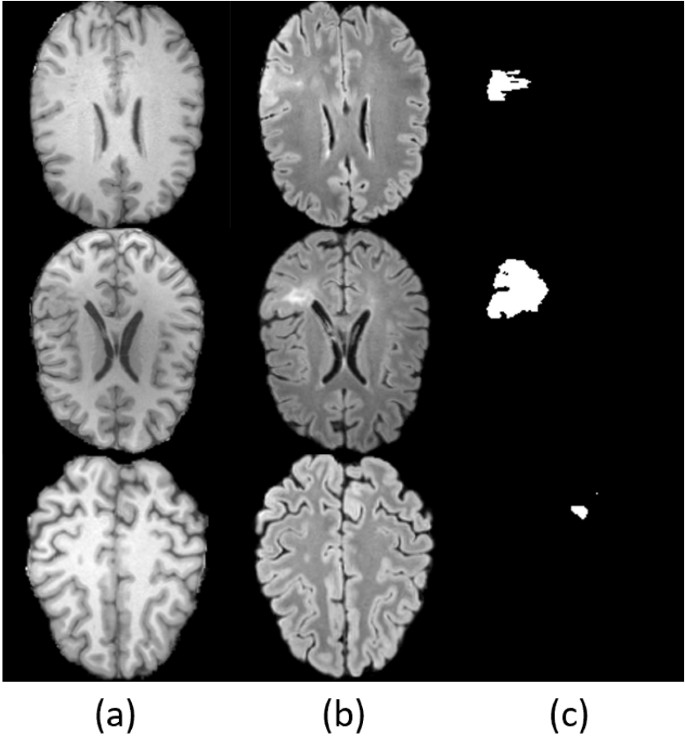

In tasks like reconstruction and modality mapping for anomaly detection, particularly where lesions occupy a small portion of the image, models often resort to a conservative identity mapping strategy. This approach leads to what’s termed as an identity shortcut, where the model reconstructs inputs with minimal alterations, overlooking subtle yet crucial abnormal features. This is particularly problematic in detecting FCD II lesions. Figure 2 illustrates the clear distinction between T1 and FLAIR images, with epileptic features being more pronounced in FLAIR.

T1 and FLAIR present different appearances at the lesion area. (a) T1 image, (b) FLAIR image, and (c) FCD lesion map.